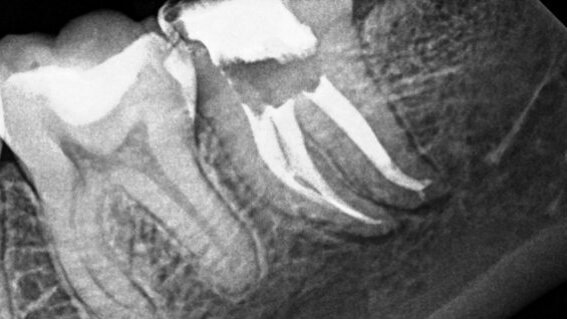

An accurate working length was established with a Root ZX (J. Morita) and an open glide path created. The canals were shaped with the WaveOne Primary (DENTSPLY) reciprocating rotary file and obturated with a resin-based sealer (Fig. 1b).

The canal was then properly shaped and obturated with an apical plug of zinc oxide eugenol sealer and gutta-percha using a warm-vertical technique. A post space was left as requested by the general dentist (Figs. 2a & b).

Upon completion it was noted that an accessory canal in the palatal and a lateral canal in the midroot of the distobuccal canals were filled with sealer (Figs. 3a & b).

The canals were obturated with a zinc oxide eugenol sealer and gutta-percha using a warmvertical technique. The post-operative radiographs showed a lateral canal filled with gutta-percha leading to the lateral radiolucency (Figs. 4a & b).